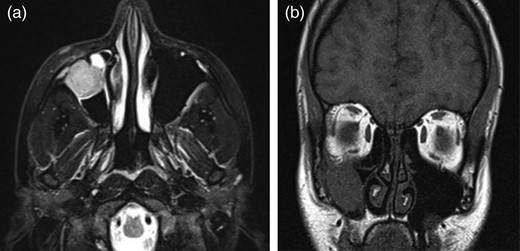

Anterior transconjunctival orbitotomy was performed for excisional biopsy and the removal of the tumor with its periosteum due to the erosion of the inferior orbital wall. The resected tumor was 3 × 3 × 3 cm and the tumor had caused lytic lesions on the inferior orbital wall. The tumor tissues resected in the surgery were fixed in 10% formalin, embedded in paraffin and then processed for light microscopy. The tissue sections were stained with hematoxylin and eosin (H&E), and examined immunohistochemically. After the surgery, the patient's diplopia with right and inferior ophthalmoparesis disappeared. At postoperative week 3, while we were waiting for the pathological diagnosis of the resected tumor, the patient visited our clinic with complaints of anesthesia and fullness on her right cheek. There was paresthesia in the region where the right infraorbital nerve innerved. Control MRI revealed a mass that invaded the anterolateral wall of the right maxillary sinus (Fig. 2a and b). In the meantime, tumor cells were positive in the membranous pattern for CD99 immunostaining and Periodic acid—Schiff (PAS) (Fig. 3a–c).

(a and b) The emergency MRI results of the patient who had complaints of infraorbital anesthesia in the postoperative week 3 revealed a mass invading the right maxillary sinus and probably compressing on the infraorbital nerve.